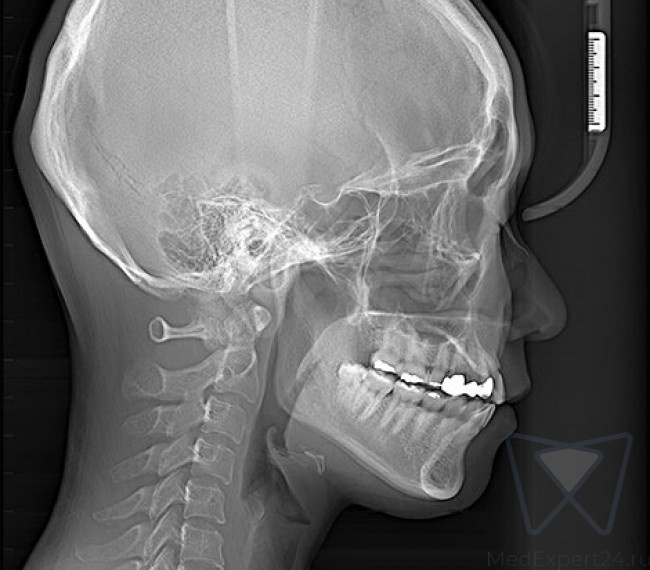

- Латеральная проекция ВНЧС

Различные варианты цефалостата:

One shot Ceph и Scanning ceph